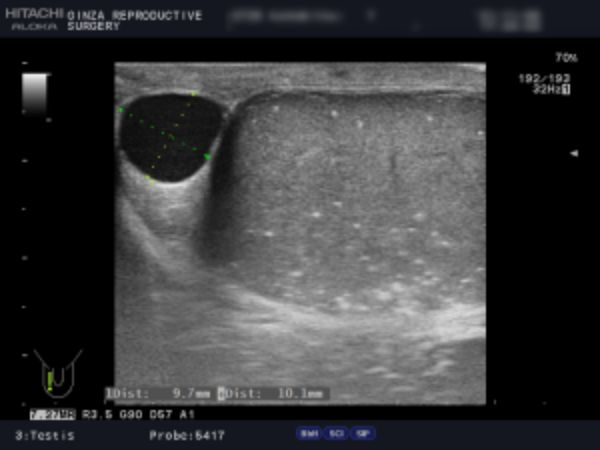

精索静脈瘤の検査は「触診」「エコー検査」によって行います。

精索静脈瘤はその重症度を「グレード」で表します。視診・触診でも度合いを判断することはできますが、正確なことはエコー検査でしか診断することはできません。

軽症の場合、手術の必要はありませんが、当院では診察で「グレード3(見てわかる:陰のうが凸凹している、腫れている)」「グレード2(触ってわかる:腫れている)」、エコー検査で精巣周辺の静脈の太さ3mm以上が複数または2.8mm以上が多数あるものを手術適応としています。

検査は、視診と触診の他、エコー検査で精巣周囲の静脈の太さを確認します。

陰嚢専用の機器を用いてエコー検査を行い、陰嚢の状態を検査します。正確に検査することで的確な手術ができ、再発の可能性を限りなく下げることができます。

エコー検査では、精巣腫瘍、精液瘤、精巣水腫、精巣内石灰化の有無などを確認します。